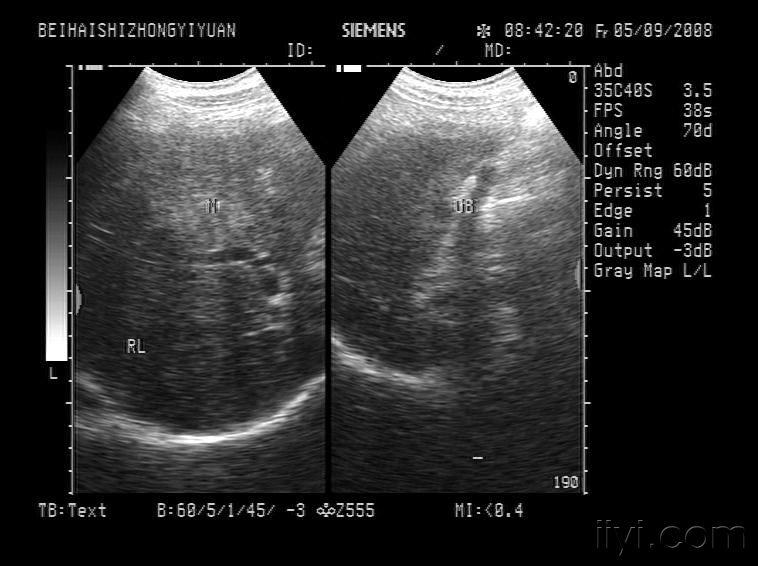

某男,35岁,体检时超声发现脾门处结节(见图),根据超声图像诊断为

图片尺寸700x425

【原创】副脾 - 超声医学讨论版 - 爱爱医医学论坛

b超检查如图所示,脾门处包块,根据超声声像图,诊断为

图片尺寸700x509